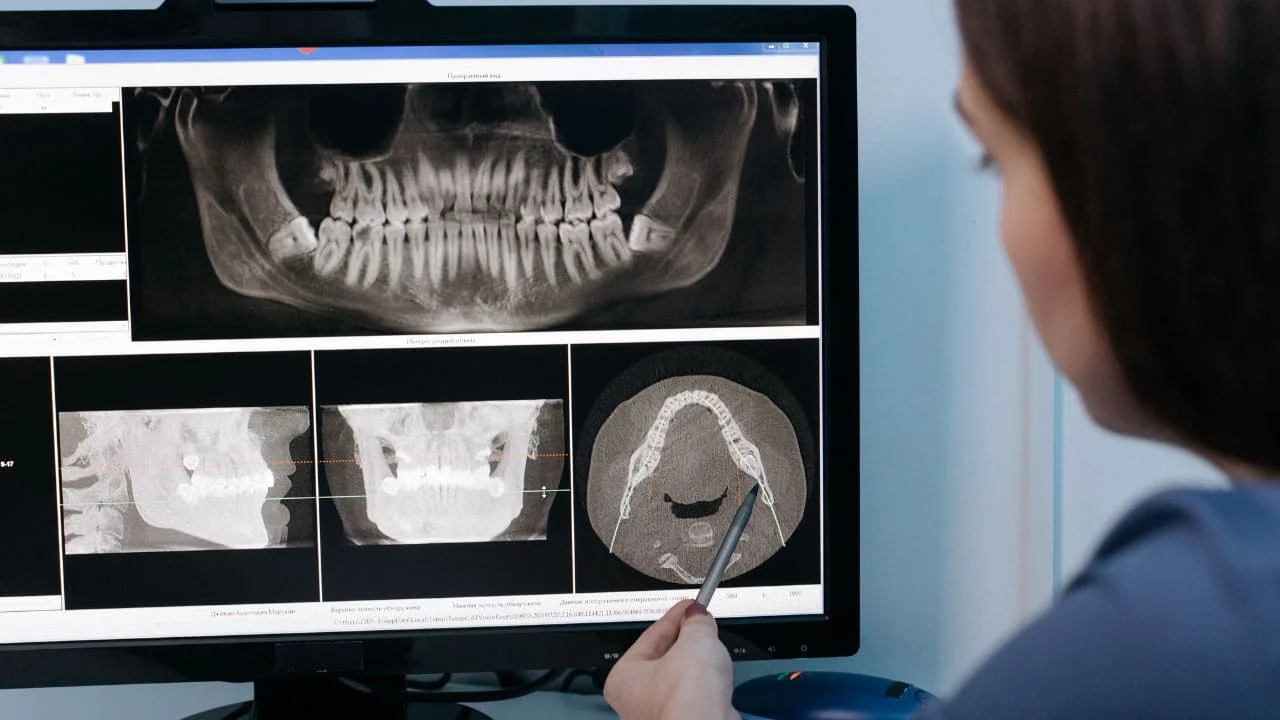

Votre dentiste commencera par examiner attentivement la zone d’extraction. Il vérifiera la présence du caillot sanguin, cherchera des signes d’infection ou d’alvéolite, et évaluera votre niveau de douleur. Une radio peut être nécessaire pour vérifier qu’aucun fragment de dent ou d’os ne soit resté en place.

- Examen clinique et radiographique